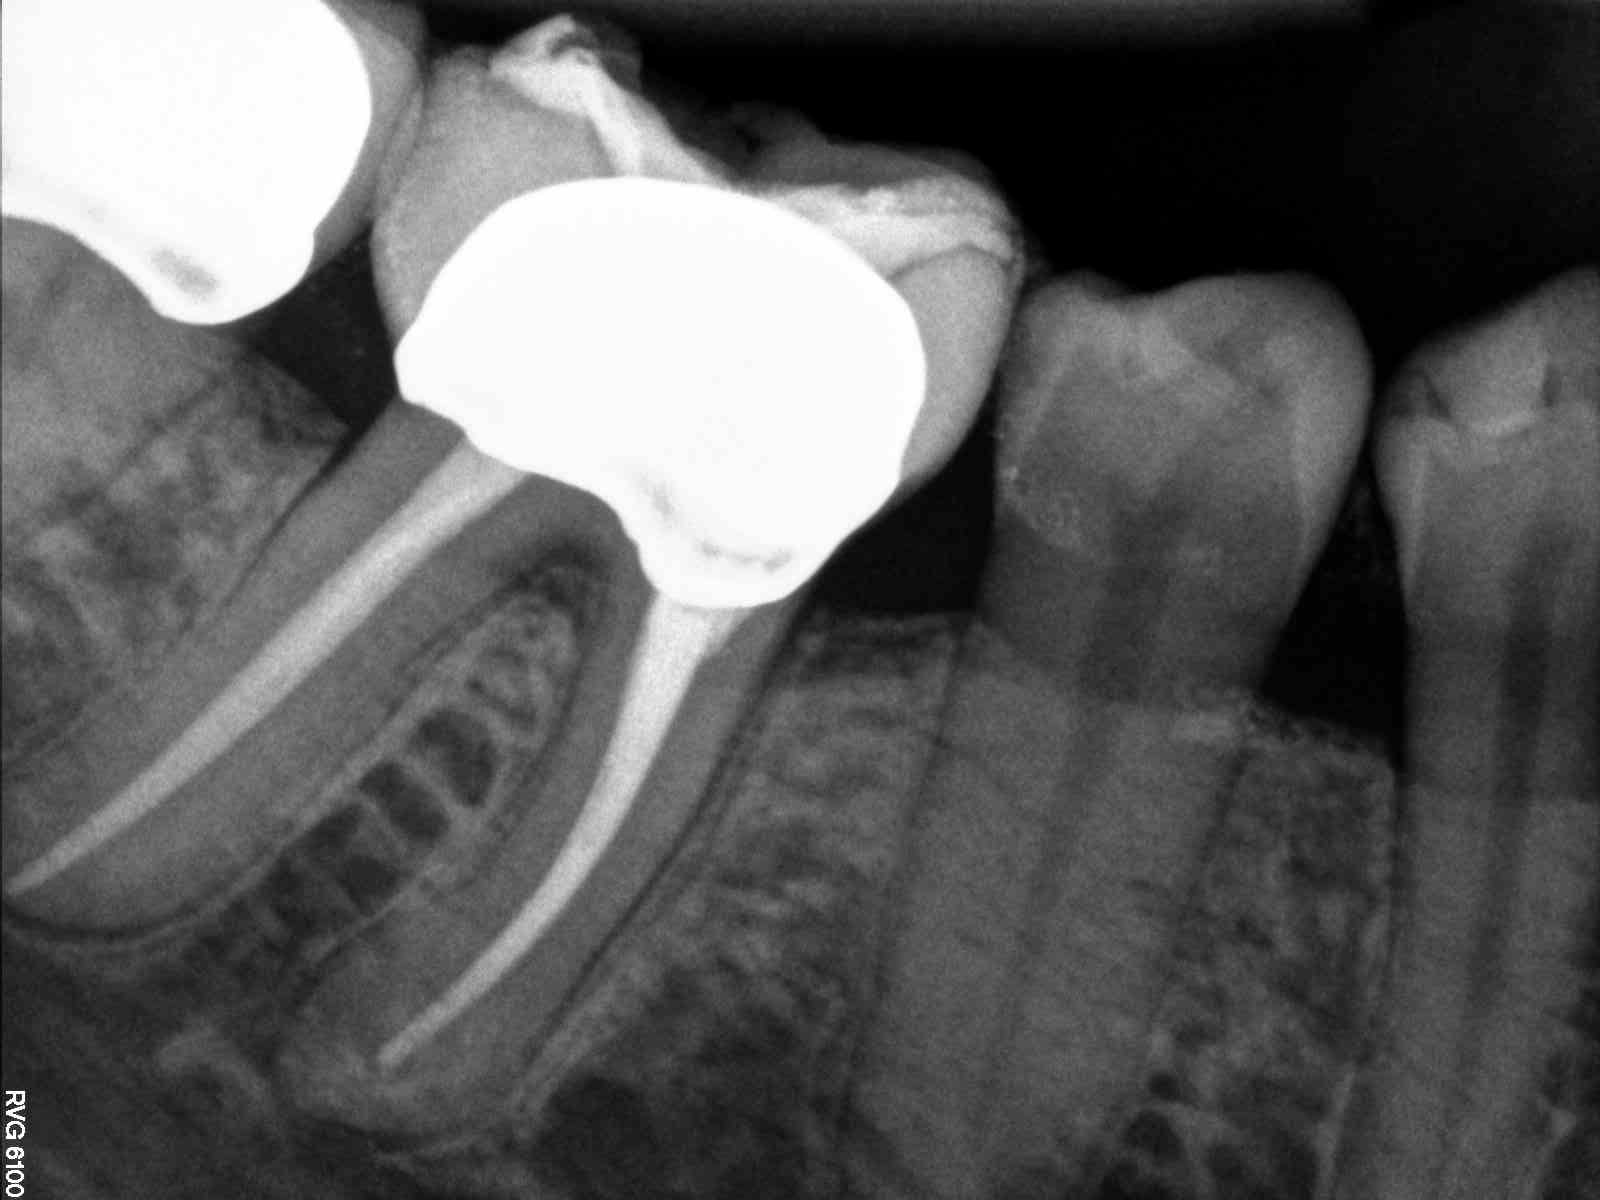

1 mesial canal, although it was ribbon shaped at pulpal floor.

| Angled can kind or see where ribbon portion canal is |